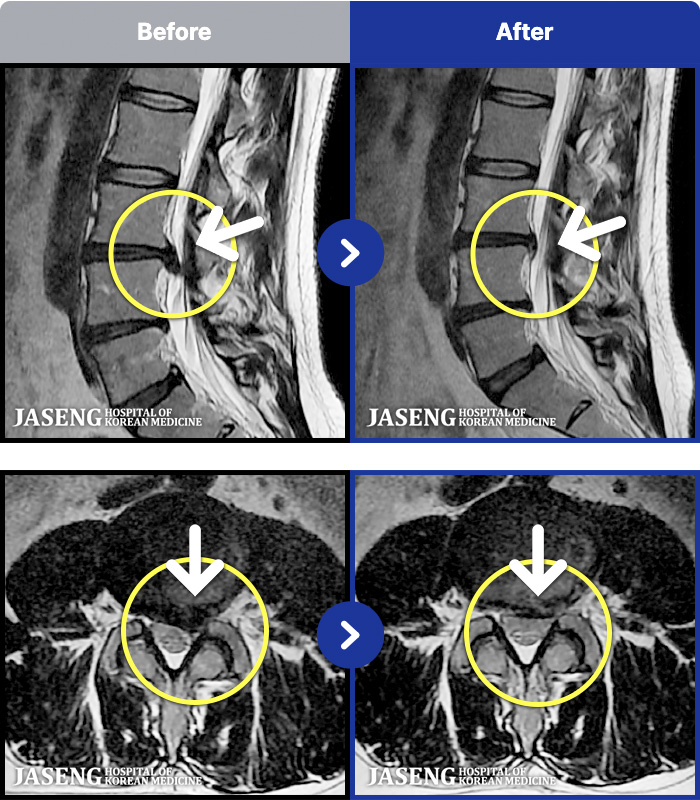

54 MRI ũ ʸ Ȯϼ.

ȯںп Ǹ ǿ ԿǾ, ο ġ ۿ Ƿ ġḦ Ͻñ ٶϴ.